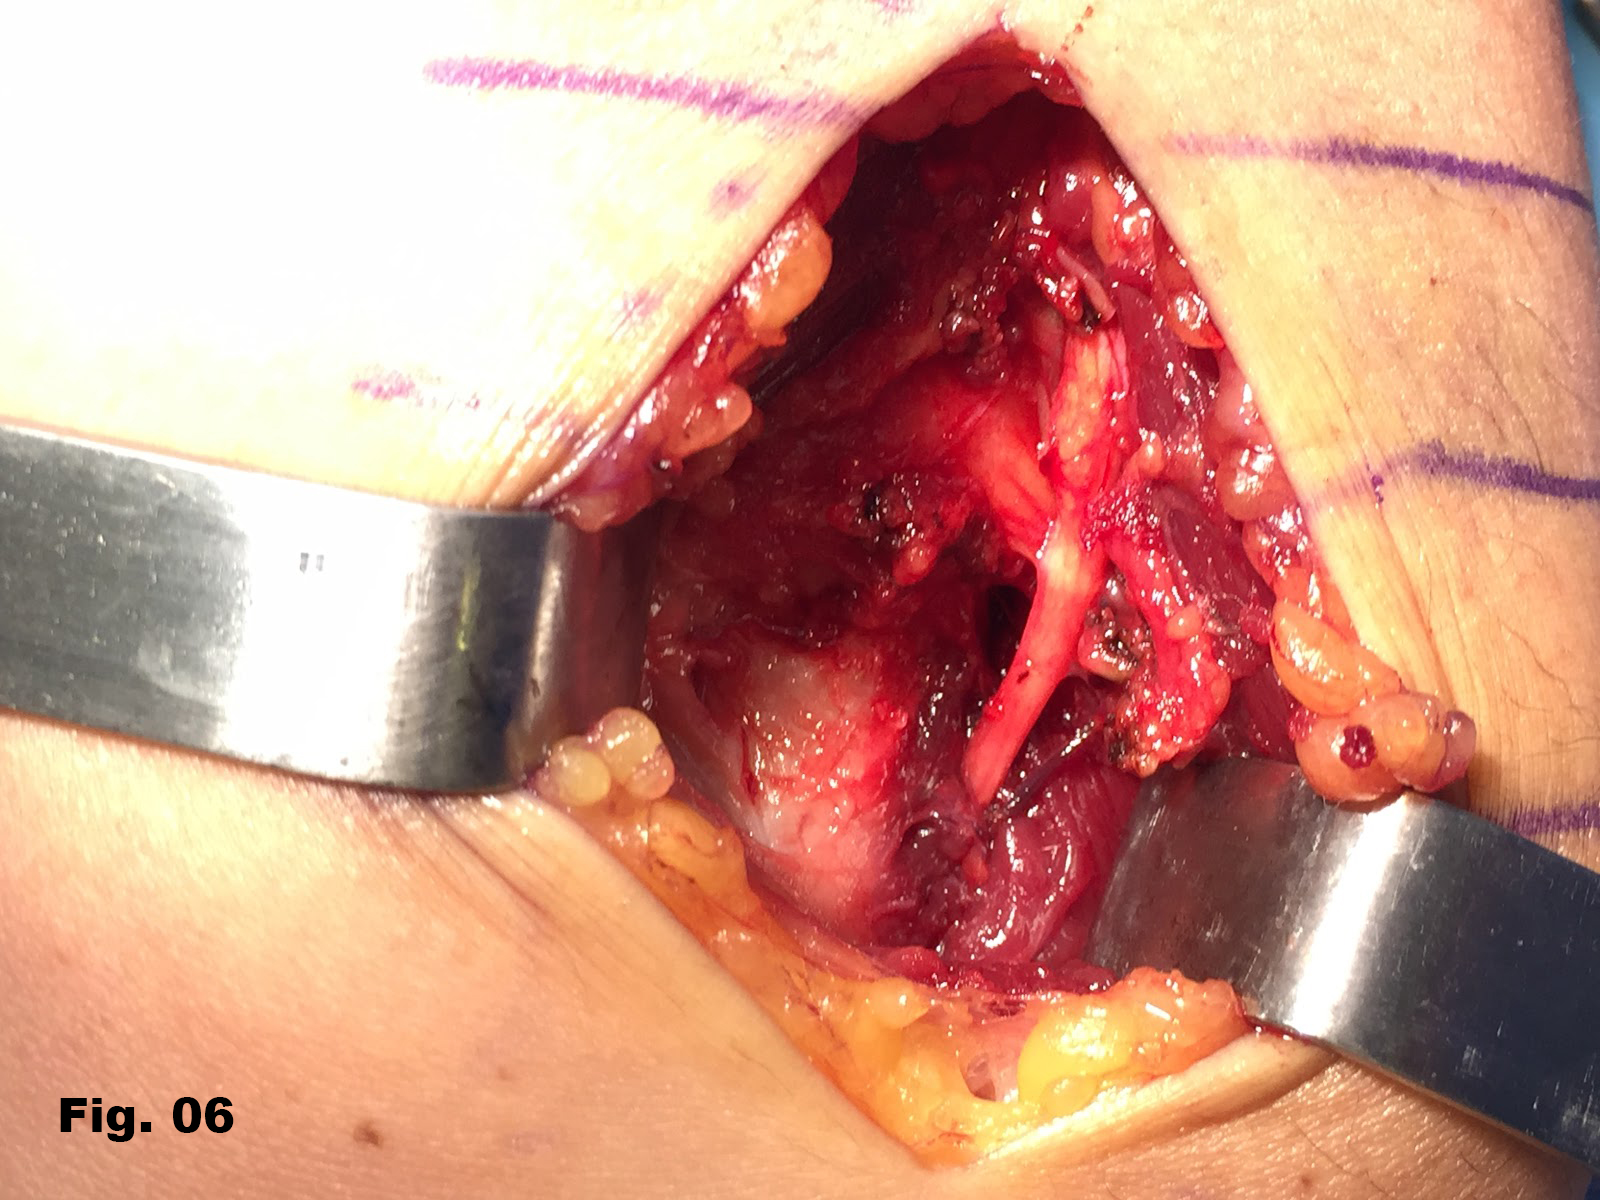

A 51-years-old healthy female, with no history of upper limb injuries, complained of an anterior and proximal left forearm tenderness associated with weakness of the extensor muscles of the forearm. An ultrasound scan was performed and demonstrated a thickened and hypoechoic posterior interosseous nerve (PIN) at the arcade of Frohse, with hypervascularization of the perineurium. In its deeper aspect, there was a subtle irregularity of the radial metaphysis (Fig1,2). The plain film showed a sessile irregularity of the anterior region of the metaphysis (Fig 3). Unenhanced MRI and CT scan were also performed. The CT scan showed the irregularity of the radius (Fig 4) and in the MRI (Fig 5), it was reported as an osteochondroma like metaphyseal lesion of the radius. Initial treatment included a corticosteroid injection around the PIN, but without decrease of symptomatology. The orthopedic surgeon then proceeded with an osteochondroma resection to release the PIN. The upper limb surgical team performed the surgery (Fig 6), and they found a thickened, hyperaemic PIN, adjacent to the osteochondroma (Fig 6,7). They resected the osteochondroma and debrided the PIN (Fig 8). The patient recovered full muscular strength and the tenderness progressively disappeared.

Fig 6: The PIN is exposed at the arcade of Frohse (AF) level, adjacent to the radial osteochondroma (OTC).